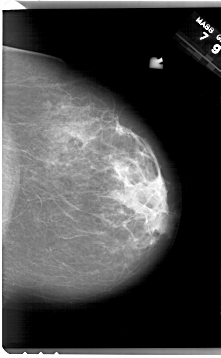

A_1626_1.LEFT_CC

LEFT_CC LINES 6871 PIXELS_PER_LINE 4231 BITS_PER_PIXEL 12 RESOLUTION 43.5 OVERLAY